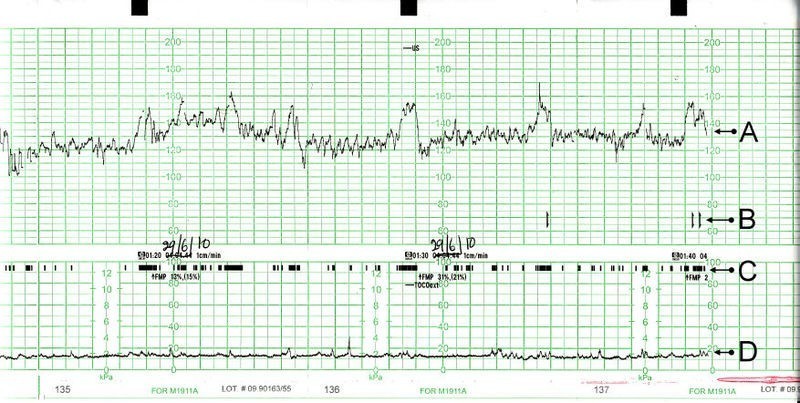

Pour ce faire, un enregistrement cardiotocographique est posé, et une échographie obstétricale par voie endovaginale est à réaliser pour mesure de la cervicométrie. On considère un col raccourci lorsqu’il est mesuré par échographie à moins de 25 mm.

Le rythme cardiaque fœtal entre compris entre 110 et 160 batt/min, donc normal

Le tracé tocographique (ligne du bas) est plat et ne montre donc pas de contractions

Le rythme cardiaque fœtal vous est présenté :